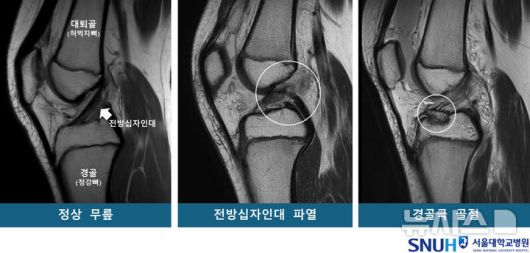

[서울=뉴시스] 정상 무릎 및 무릎 부상 환자의 MRI. (사진= 서울대병원 제고얘 |

연구팀은 소아청소년을 각 53명씩 ▲전방십자인대 파열군 ▲경골극 골절군 ▲대조군(정상 무릎)으로 구분하고 연령·성별을 매칭했다. 이후 자기공명영상장치(MRI)를 재구성한 3차원 영상을 바탕으로 14개의 해부학적 지표를 분석했다.

연구팀은 경골 바깥쪽 관절면의 경사가 가파를수록 무릎에 무게가 실릴 때 대퇴골(허벅지뼈)이 바깥쪽으로 회전하며, 그 결과 전방십자인대가 과부하되어 파열이나 경골극 골절로 이어질 수 있다고 설명했다. 또 대퇴과간 절흔 폭이 넓을 경우, 전방십자인대가 대퇴골과 덜 충돌하기 때문에 파열 위험이 낮아지는 경향이 있다고 밝혔다.